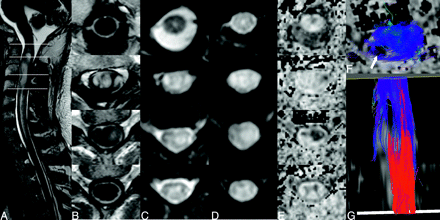

Examples of DTI and tracking in the spinal cord are given in Figs 4–8, illustrating some preliminary observations based on the small number of subjects studied to date. Acquisition during quiescence results in greater consistency of the dominant direction of diffusion tensor laying in the rostral-cranial throughout the spinal cord. This is seen in the color-coded FA maps and first eigenvector displays from a healthy control subject (Fig 4). In all control subjects and patients, the spinal cord was clearly distinguished from adjacent fluid in the DTI data and maps. The expected butterfly configuration of the central gray matter however, was visible on most sections for each volunteer only with acquisition timed to the quiescent period.

Comparison of diffusion tensor properties obtained without (top row) and with (bottom row) optimized cardiac triggering, illustrated in midspinal coronal reformat of axial section data. The CSF space and CSF-spinal cord interface are better defined in the low b-value data (D versus A) allowing the low FA in the CSF space to be better appreciated (F versus C). FA maps (B and E) color-coded to reflect the orientation of the first eigenvector (blue, caudal-cranial; green, anteroposterior; red, right-left) show greater consistency between sections when the proposed trigger window is used. This is also seen when examining the orientation of the eigenvectors directly overlaid on a gray-scale FA map (F versus C).

Fiber tracking results representative of a healthy adult obtained using the optimized trigger timing detailed above are shown in Fig 5. When the ROI contains the entire cross-section of the spinal cord in the most superior (or inferior) section, it is notable that relatively few fibers extend from end to end of the comparatively short imaging volume (typically 2-3 vertebral bodies in the current implementation). At least part of this attrition appears to be due to fiber convergence and crossing at the emergence of nerve roots (Fig 5B). In light of the residual errors in the eigenvectors seen in Fig 4, however, one cannot rule out the presence of artifactual attrition as well. By limiting the initial ROI to the lateral white matter in the most superior section, a subset of the tracks can be more clearly seen. These tracks remain lateralized, and with a suitable stopping threshold, the depicted fibers do not appear to enter the central gray matter of the spinal cord. Blue in Fig 5B, -C, depicts the cranial-caudal orientation of the local first eigenvector, so the dominant direction of diffusion is readily apparent. Intermittent zones of green and red correspond to the origins and progressions of nerve roots.

Fiber-tracking results from a healthy control (A) with the entire cross-section of the spinal cord in both the superior (blue fibers) and inferior section (red fibers) used as seeding regions. Few tracks extend from end to end of the scan volume (covering slightly more than 2 vertebral bodies). Color coding the same fibers in accordance with local orientation of the first eigenvector (blue, rostral-caudal; red, left-right; green, anteroposterior), many of the fibers appear to converge on an emerging nerve root, suggesting that fiber crossing may be present. Restricting seeding to the lateral white matter in the in the most superior section (C) shows no penetration of these tracks into the central regions of the cord.